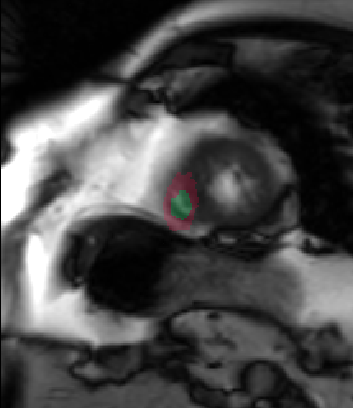

Table 2 summarizes the results of our method for RV segmentation in terms of image-based metrics. The results show that the algorithm performs better at ED than ES. This can be explained by the fact that the image quality is higher at ED than at ES. By analyzing the DM and HD on a slice-basis, it can be seen that the proposed method has a high performance on basal slices, with an average and . However, the segmentations on apical slices are of lower quality affecting the overall DM and HD scores. Figure 3 shows segmentation results in six different cases obtained from the challenge that illustrate the differences between basal and apical segmentations.

The results show that the method perform well on average but there are some cases in which it fails. In particular, our method has a very high performance on the basal slices, whereas the scores obtained for apical slices are lower (Figure 3). These can be explained by two factors: 1) The image quality at the apical slices is rather low. As the registration, the atlas ranking and the label fusion are intensity-based, poor image quality can affect the results, and 2) the regions to be segmented at the apical slices are rather small, which implies that the atlases’ masks are also small at these slices. When the masks are used in the registration process to supress undesired structures, the remaining information is insufficient, causing the intensity-based registration, rigid or non-rigid, to fail.